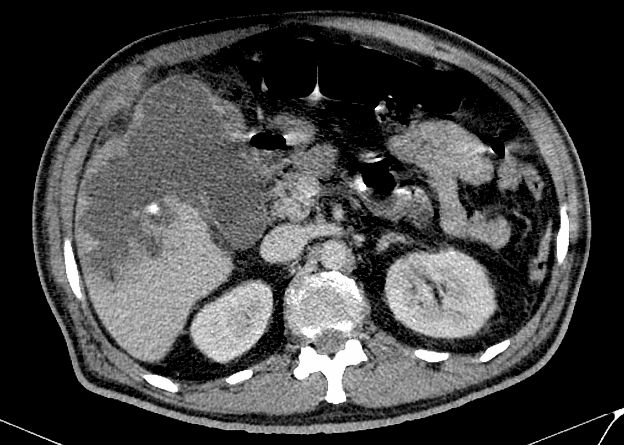

Viêm túi mật

» Thông tin: Nam giới – 60 tuổi.

» Lâm sàng: Đau bụng cấp.

# Viêm túi mật cấp biến chứng vỡ => Apxe gan.